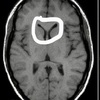

13

2

A

Corpus Callosum